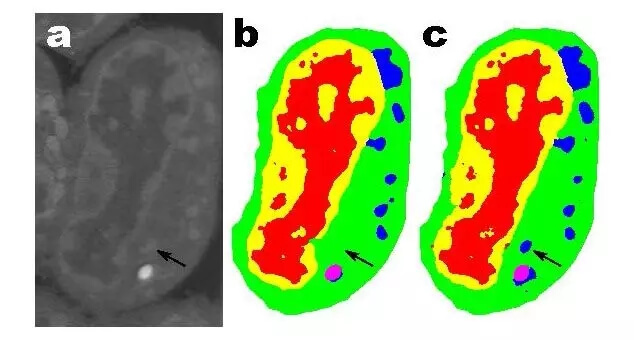

小鼠淋巴母细胞的切片。(a)原始图像;(b)人工切割得到的切片;(c)100 层的 MS-D 网络的输出(数据来自 A.Ekman, C. Larabell, National Center for X-ray Tomography)

该算法还可用于理解生物细胞内部结构,这一应用也非常有前景。使用 Pelt 和 Sethian 的 MS-D 方法,仅需要七个细胞的数据,就可确定该细胞的内部结构。

国家 X 射线断层成像中心主任、加利福尼亚大学旧金山医学院的教授 Carolyn Larabell 说:「我们实验室中的主要工作是了解细胞的形态结构是如何影响和控制细胞行为的。我们花费无数小时手动分割细胞,以提取细胞结构并识别细胞间的差异,如识别健康细胞和病变细胞间的差异。新算法可能彻底改变我们对疾病的认知能力,而这种算法也是绘制人类细胞图谱的主要工具,绘制人类细胞图谱是扎克伯格和他的夫人赞助的一项全球合作项目,旨在绘制出健康人体中所有的细胞。」